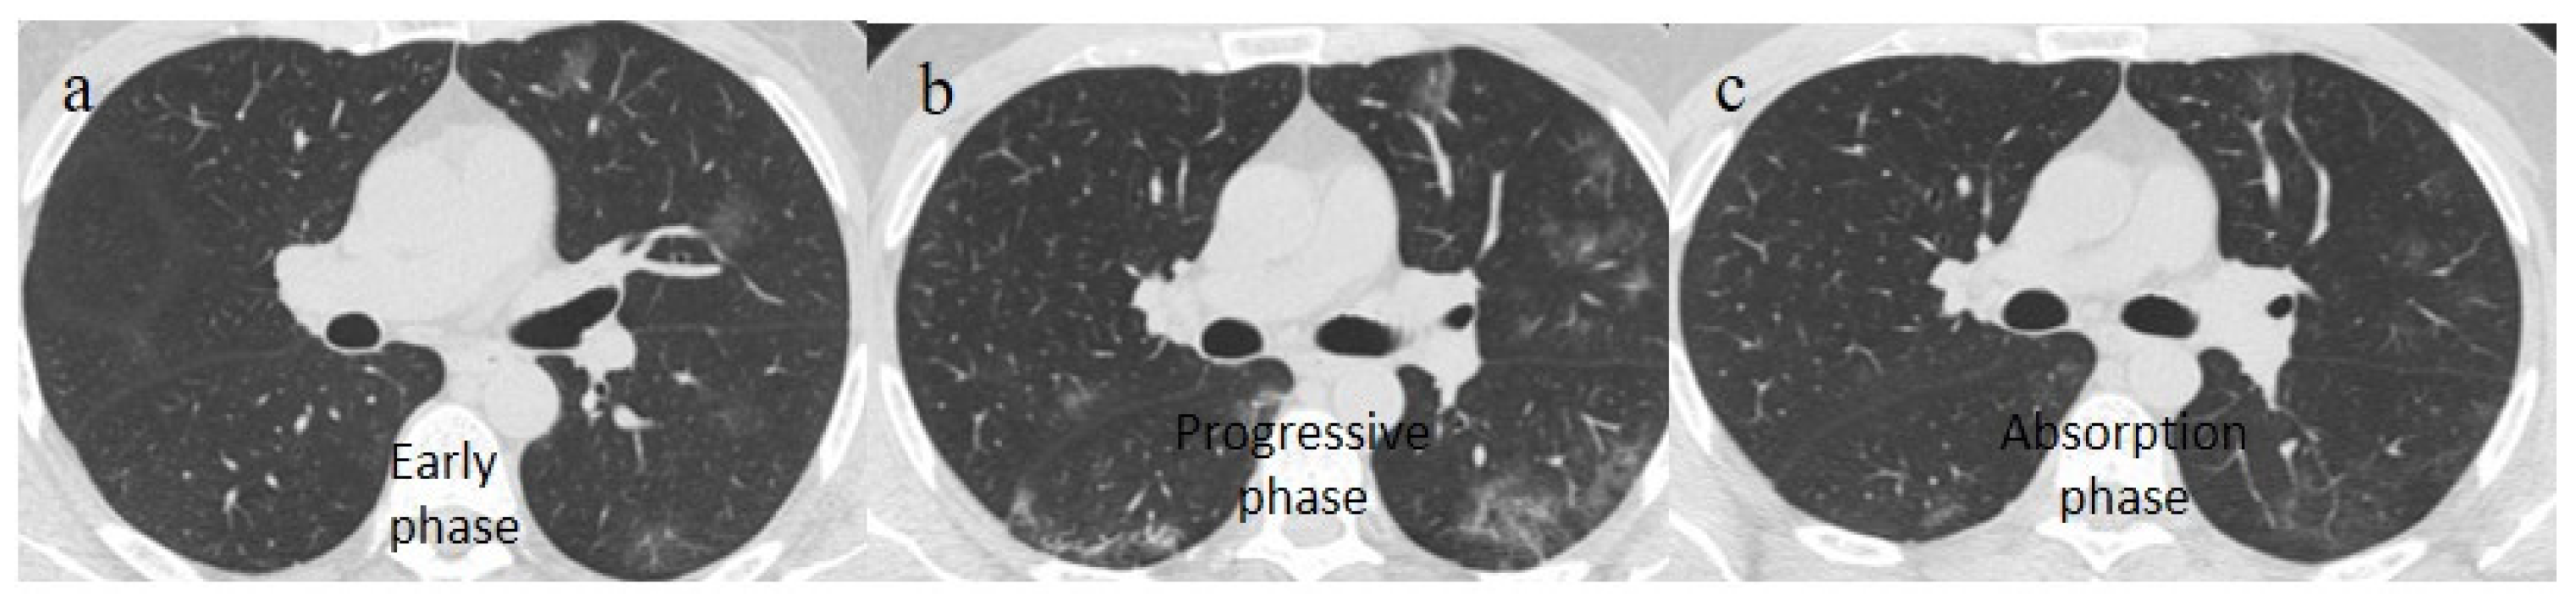

- Wang, Y.; Dong, C.; Hu, Y.; Li, C.; Ren, Q.; Zhang, X.; Shi, H.; Zhou, M. Temporal Changes of CT Findings in 90 Patients with COVID-19 Pneumonia: A Longitudinal Study. Radiology 2020, 296, E55–E64. [Google Scholar] [CrossRef]

- Hu, Q.; Guan, H.; Sun, Z.; Huang, L.; Chen, C.; Ai, T.; Pan, Y.; Xia, L. CT features and temporal lung changes in COVID-19 pneumonia in Wuhan, China. Eur. J. Radiol. 2020, 128, 109017. [Google Scholar] [CrossRef]

- Li, X.; Zeng, W.; Li, X.; Chen, H.; Shi, L.; Li, X.; Xiang, H.; Cao, Y.; Chen, H.; Liu, C.; et al. CT imaging changes of corona virus disease 2019(COVID-19): A multi-center study in Southwest China. J. Transl. Med. 2020, 18, 154. [Google Scholar] [CrossRef]

| Typical Appearance | GGOs with a crazy-paving pattern and consolidations in a peripheral and posterior or central-peripheral distribution; multilobar involvement; vascular enlargement, the halo and reversed halo sign; subpleural and parenchymal bands; and architectural distortion. They were predominant since the Delta wave. |

| Typical findings of interstitial pneumonia with peripheral or peripheral central distribution from the wild/type variant since Delta variant |

| Absence of pneumonia or atypical findings during the Omicron wave | |||